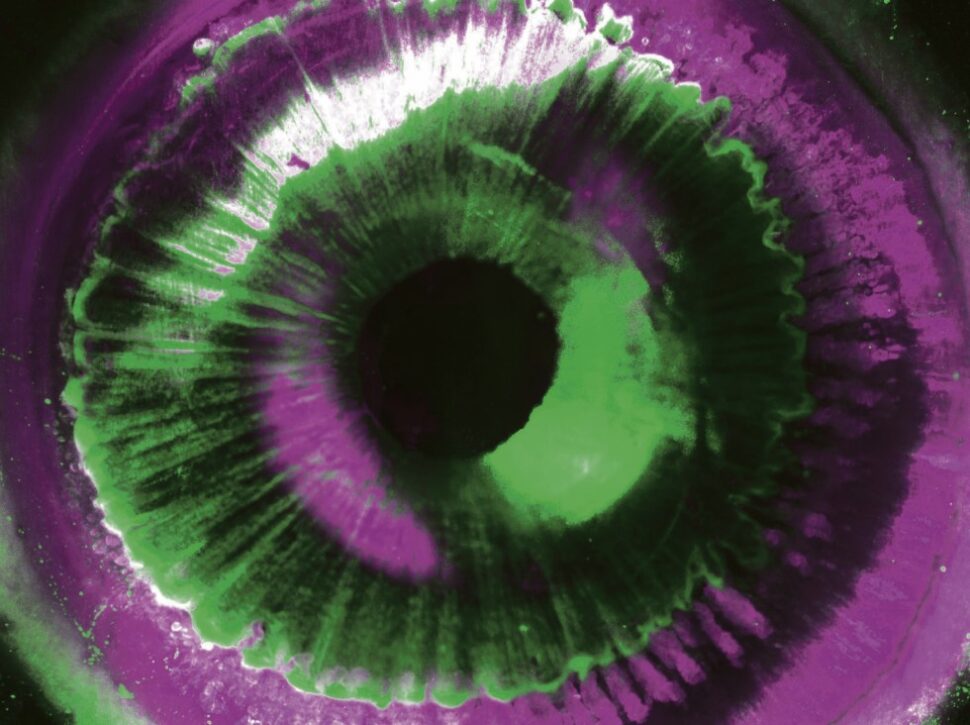

Bildgebung: Organstruktur wird sichtbar gemacht

Damit menschliche Organe zum Beispiel per 3D-Druck nachgebildet werden können, muss zunächst deren komplexer Aufbau dargestellt werden.

Foto: Helmholtz Zentrum München / Ertürk Lab